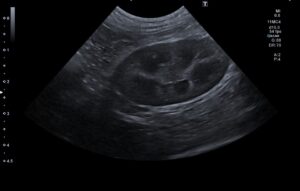

検査の結果、左の尿管結石と閉塞が見られました。

術後のエコーで腎臓の腎盂拡張は改善されています。